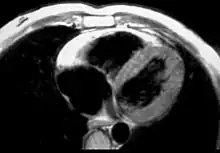

MRI

Fatty infiltration of the RV free wall can be visible on cardiac MRI. Fat has increased intensity in T1-weighted images. However, it may be difficult to differentiate intramyocardial fat and the epicardial fat that is commonly seen adjacent to the normal heart. Also, the sub-tricuspid region may be difficult to distinguish from the atrioventricular sulcus, which is rich in fat.

Cardiac MRI can visualize the extreme thinning and akinesis of the RV free wall. However, the normal RV free wall may be about 3 mm thick, making the test less sensitive.